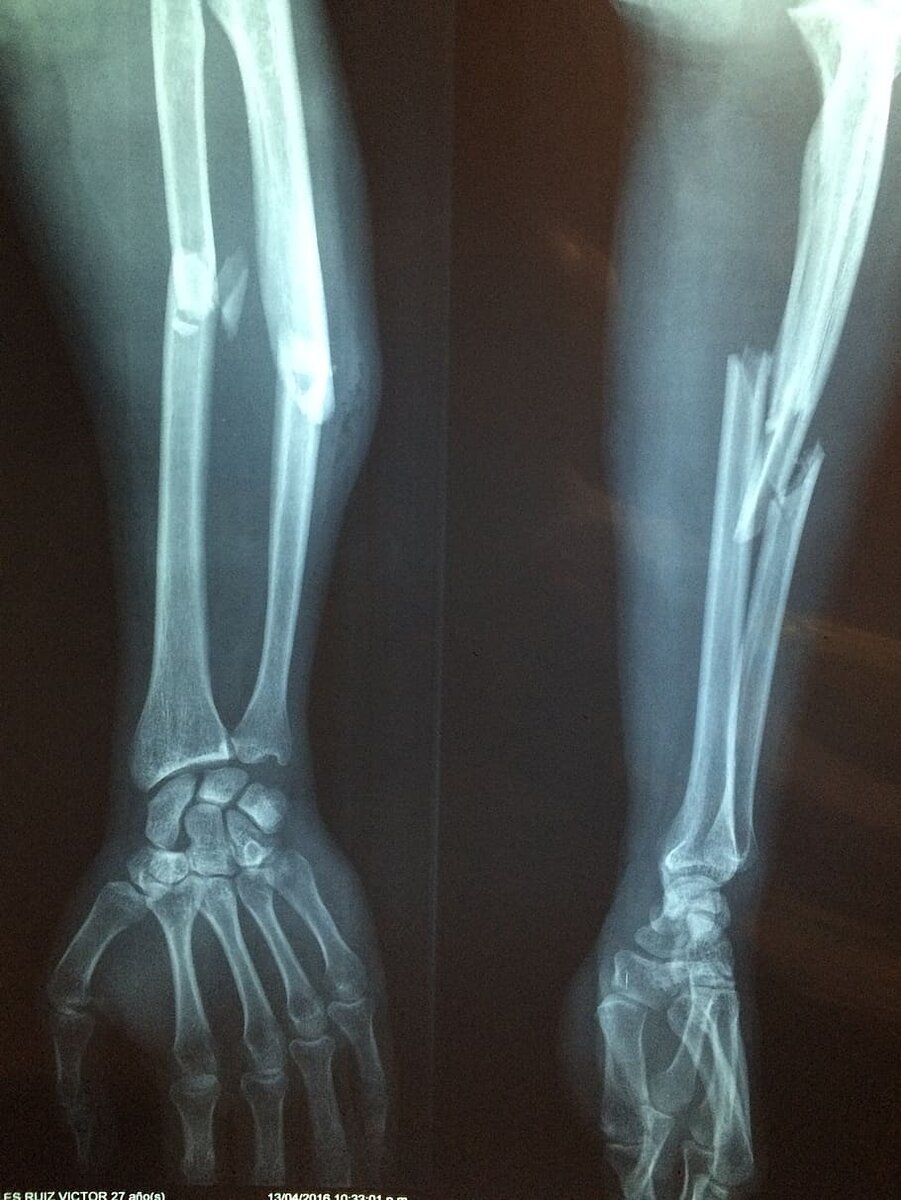

Неправильная техника выполнения упражнений с большими весами может грозить не только повреждением мышц и связок, но и серьезными переломами